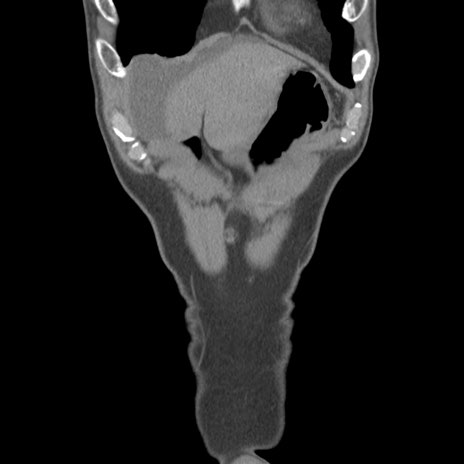

症例56 CT(冠状断像)

脂肪ウインドウ